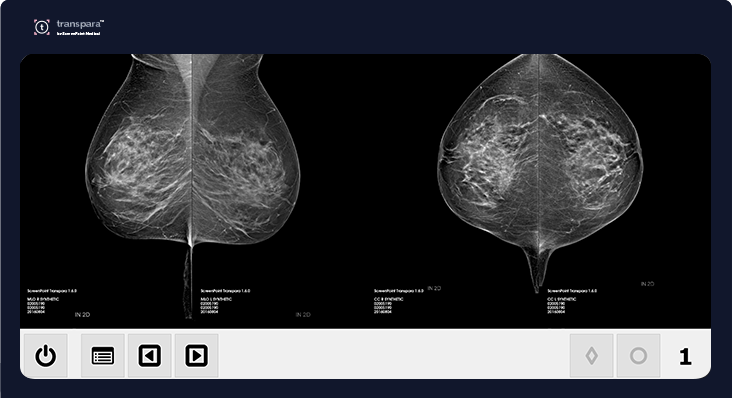

AI software used in this study

The Transpara Exam Score is an image-based risk tool that categorizes exams using a 10-point scale and is used for concurrent reading of mammograms. The higher the score, the higher the risk of cancer in the mammogram. Clinical research conducted with Transpara shows that scores between 1 - 7 (Low Risk) have a 99.97% negative predictive value. The Volpara TruDensity AI algorithm uses a combination of x-ray physics and machine learning to generate an accurate volumetric measure of breast composition to eliminate variability that can arise from human interpretation.

Used by leading centers globally, Transpara has been used to analyze more than 4 million mammograms. Research shows that up to 45% of interval cancers can be found earlier using Transpara, while helping to reduce workload and optimize workflow